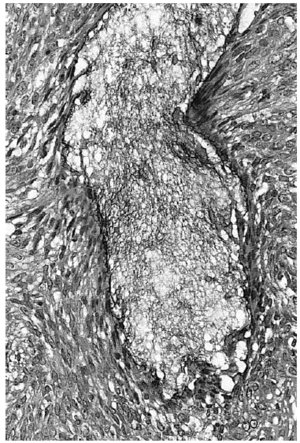

En dos biopsias previas sólo pudo apreciarse una epidermis psoriasiforme y un inflitrado linfocitario de predominio perifolicular, hallazgos que se consideraron compatibles con rosácea. Se instauraron tratamientos con metronidazol, tópico y oral, y con tetraciclinas orales, sin que se observara ninguna mejoría. En una tercera biopsia se encontaron hallazgos similares, pero con áreas de degeneración mucinosa a nivel de los folículos polisebáceos (figs. 2 y 3). Las tinciones de hierro coloidal y azul Alcián (pH 2,5) confirmaron la presencia de mucina a nivel folicular. El infiltrado seguía siendo foliculotrópico, sin atipias nucleares en los linfocitos ni epidermotropismo. Considerando estos hallazgos histológicos, la ausencia de otras dermatosis, la exclusión de procesos linfoproliferativos sistémicos y la evolución de la lesión se estableció el diagnóstico de mucinosis folicular primaria. La lesión fue tratada con PUVA (psoraleno y luz ultravioleta) con escasa mejoría.

Fig. 3.--Acumulación de mucina en uno de los folículos pilosebáceos. Los linfocitos que infiltran el epitelio folicular no muestran atipia nuclear